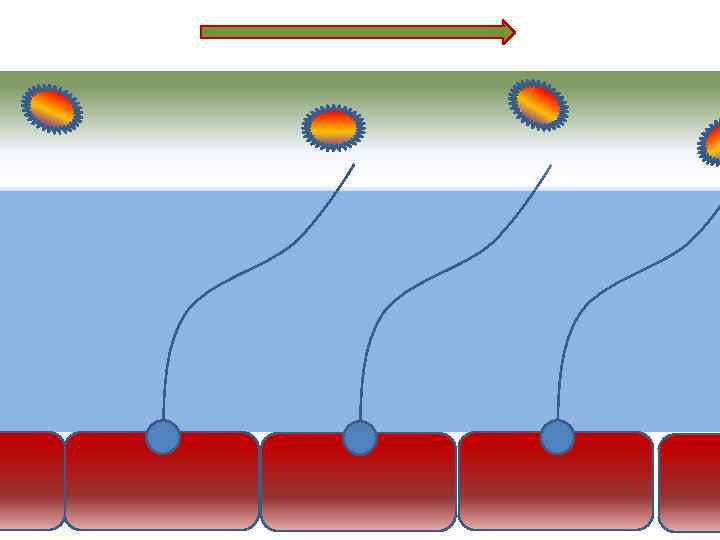

Механизм защиты легкого Слизь (зеленый цвет) нейтрализует и связывает патогенную флору(синий цвет) Слизь – это барьер между клетками и патогенной флорой Слизь – это транспортное средство

Механизм защиты легкого Слизь (зеленый цвет) нейтрализует и связывает патогенную флору(синий цвет) Слизь – это барьер между клетками и патогенной флорой Слизь – это транспортное средство